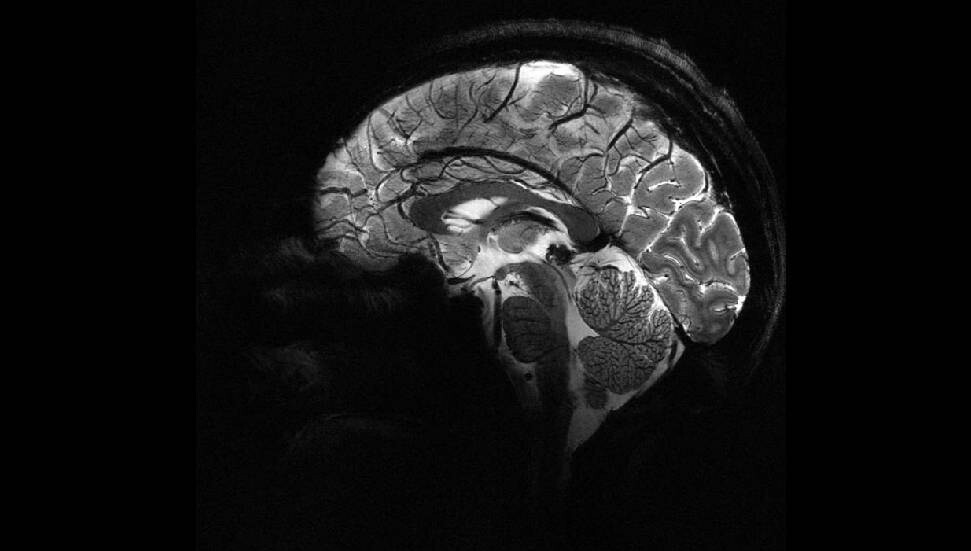

Nottingham Üniversitesi’nden bilim insanları, UK Biobank’ta yer alan 15 binden fazla yetişkinin verileriyle sağlıklı beyin yaşlanmasını tanıyan bir yapay zekâ modeli geliştirdi. Model, pandemiden önce tarananlarla, önce ve pandemi sırasında taranan iki grubun beyin yaşlarını karşılaştırdı.

Araştırmaya göre, pandemi sürecinde insan beyninin yaşlanma hızı ortalama 5,5 ay öne çekildi.